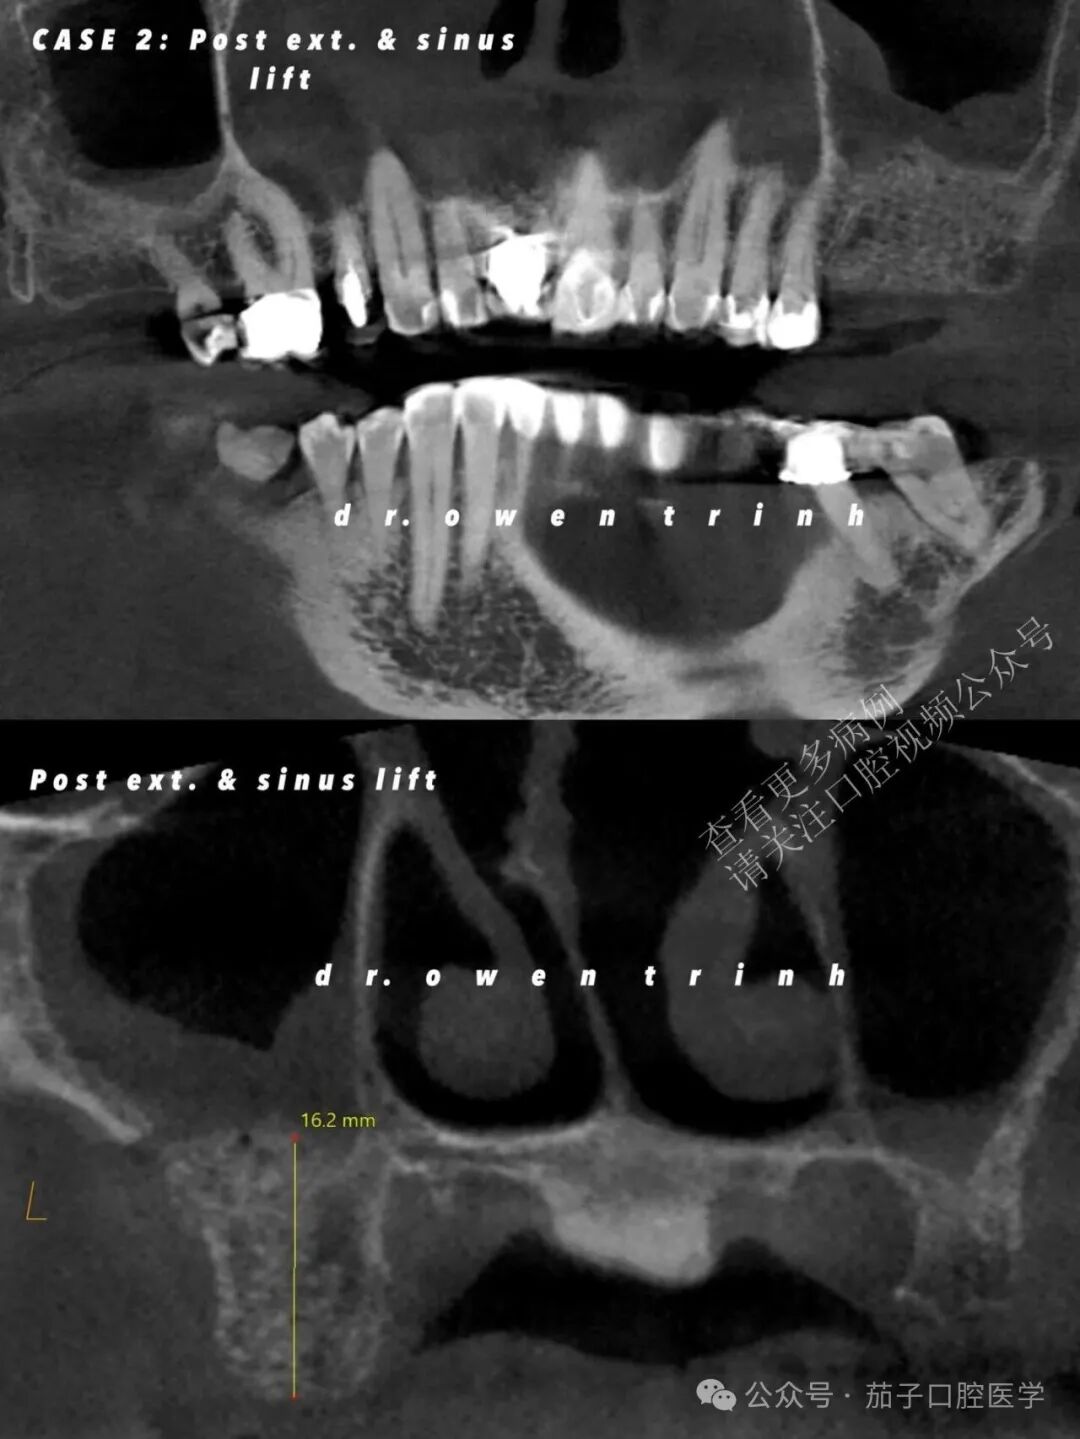

病例二

CBCT显示慢性根尖脓肿,已破坏上颌窦皮质底壁及#14与#15牙间的全部邻间壁。患者同意接受拔牙联合外侧上颌窦提升术,为后续种植体植入做准备。